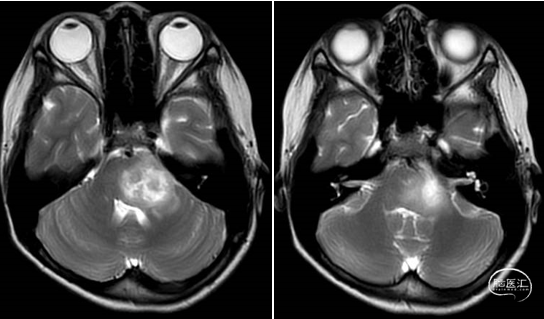

术前MRI

术后MRI